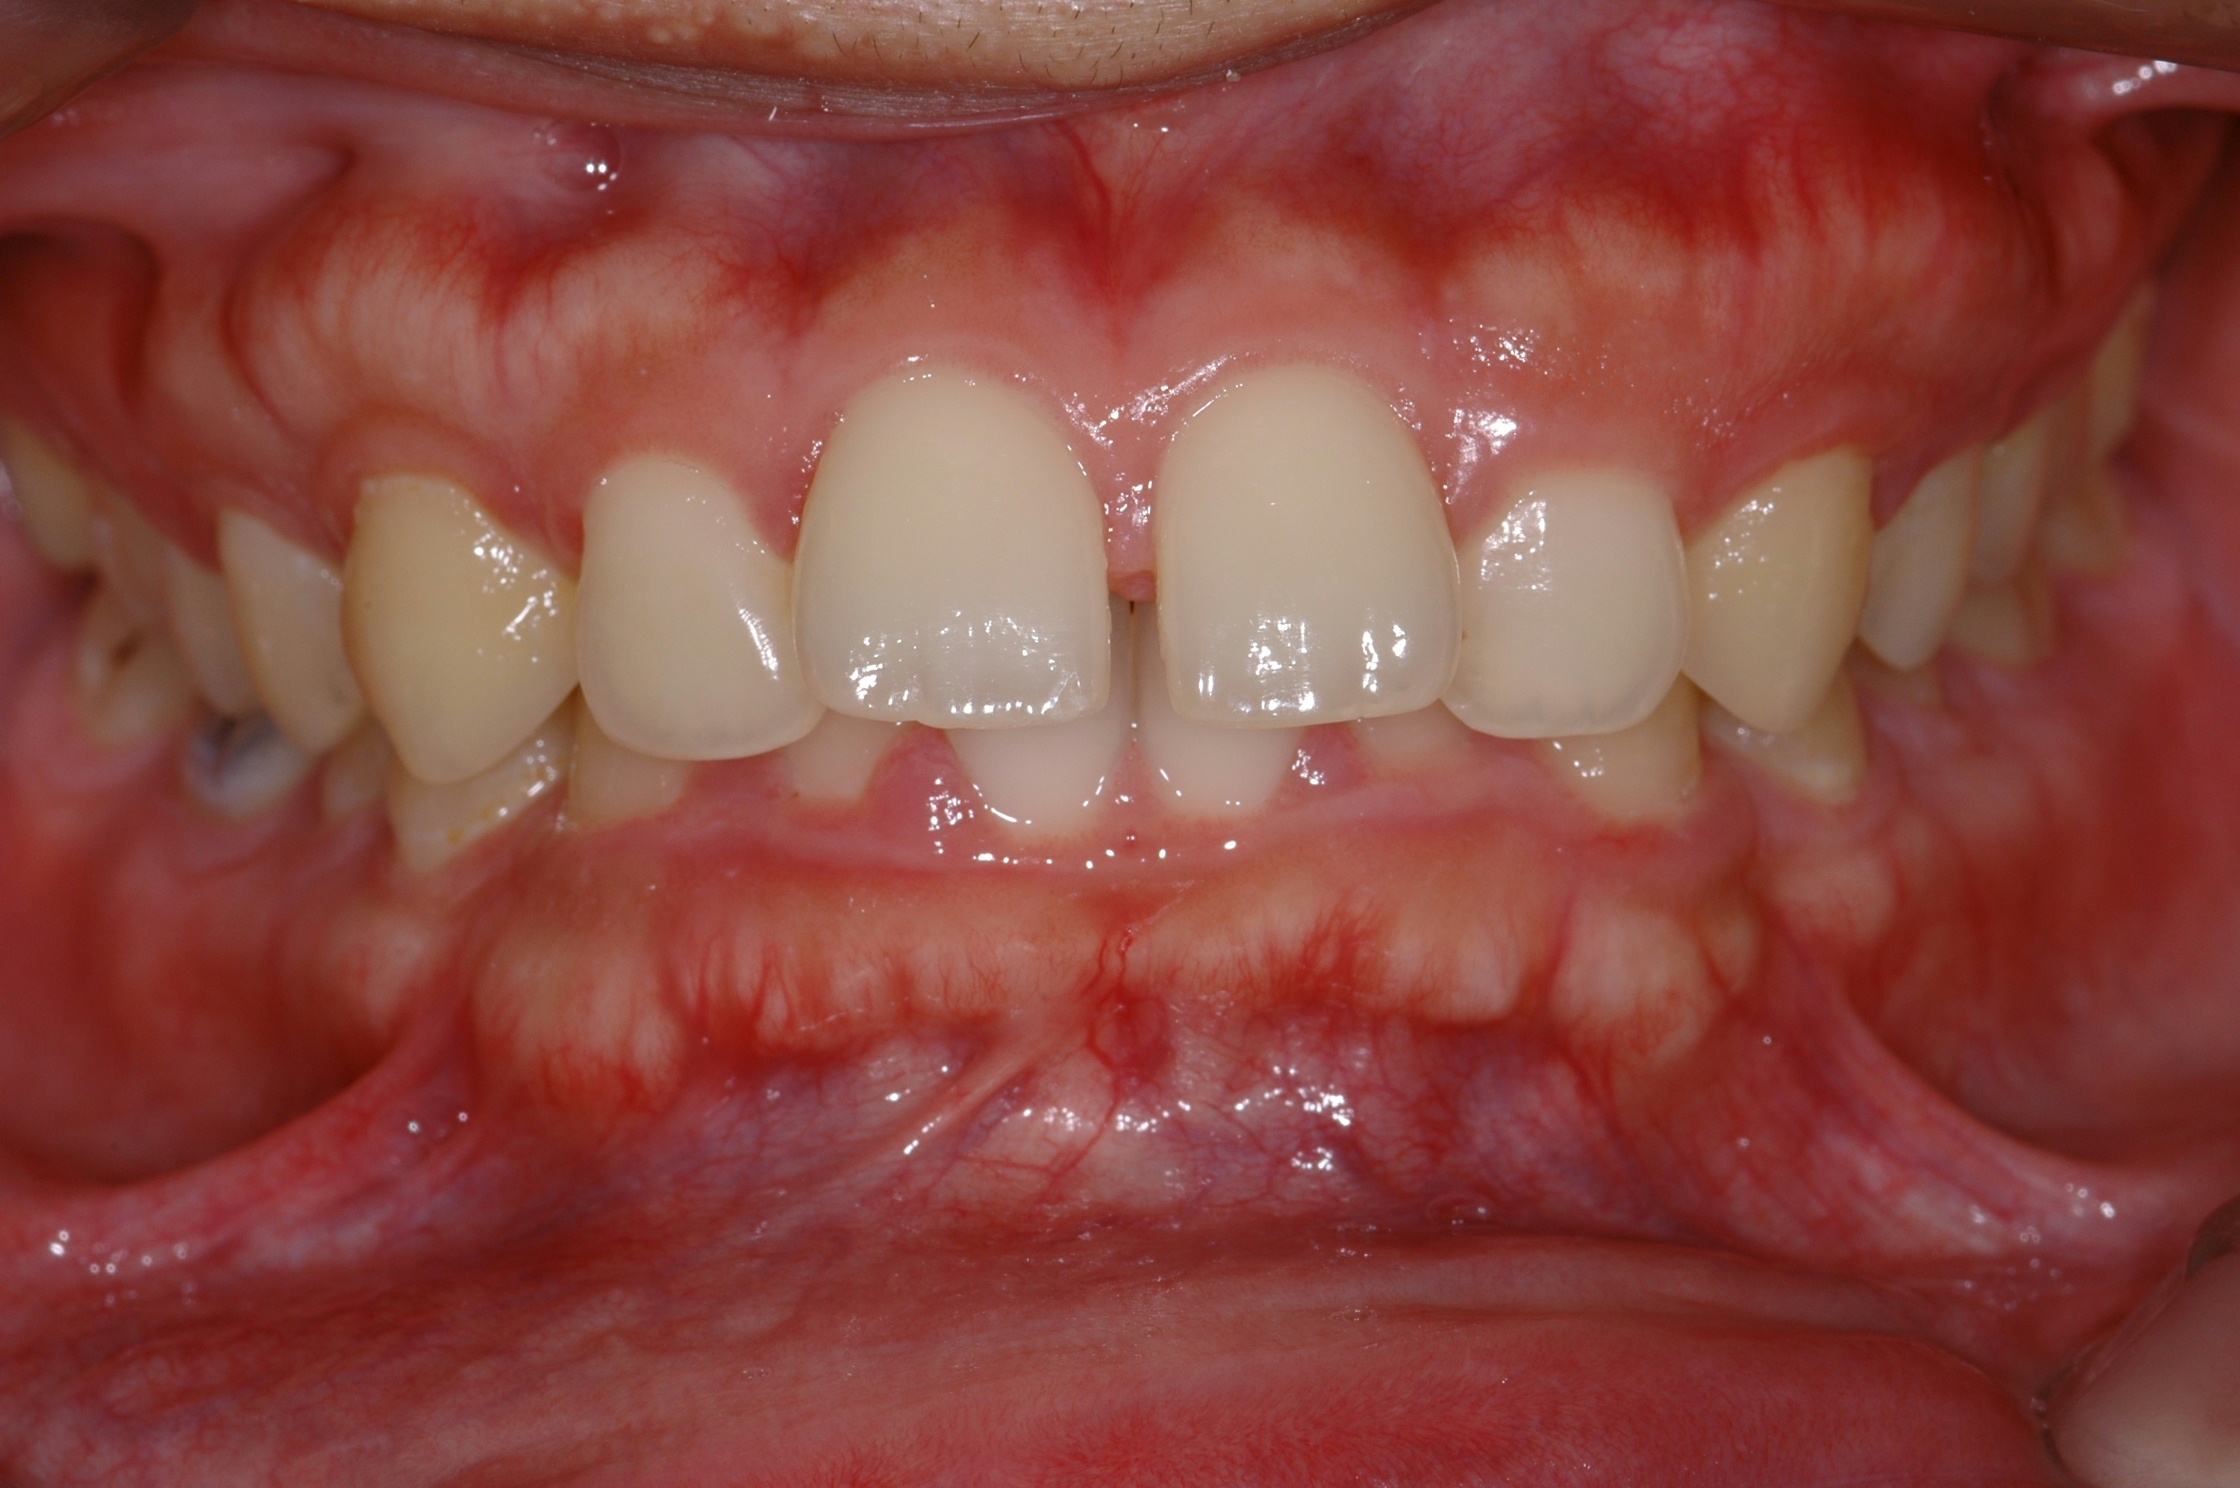

치료 후 사진입니다.